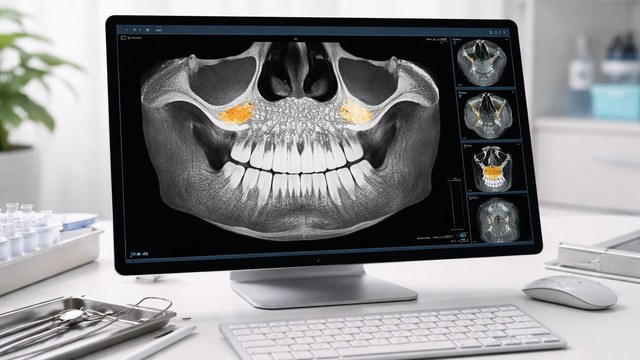

שתל דנטלי הינו תחליף מלאכותי לשורש שן המהווה בסיס לחיבור ועיגון אלמנט שיקומי כגון תותבת או כתר. שתלים דנטליים לרוב עשויים סגסוגת (תרכובת מתכות) טיטניום וצורתם דמויית בורג. מדובר בדרך הטובה ביותר הקיימת כיום להשלמה של שיניים שאבדו. השתל הבורגי מוחדר אל העצם האלואולרית Alveolar bone ע"י קידוח של חריר והברגתו של השתל פנימה כך שבסיום ההברגה השתל כולו מוקף ונמצא בעצם. החיבור של הטיטניום אל העצם יוצר קשר מבני ופונקציונלי בין העצם החיה לבין השתל. במקרים של חוסר עצם יתכן ונאלץ לבצע השתלת עצם BONE AUGMENTATION.